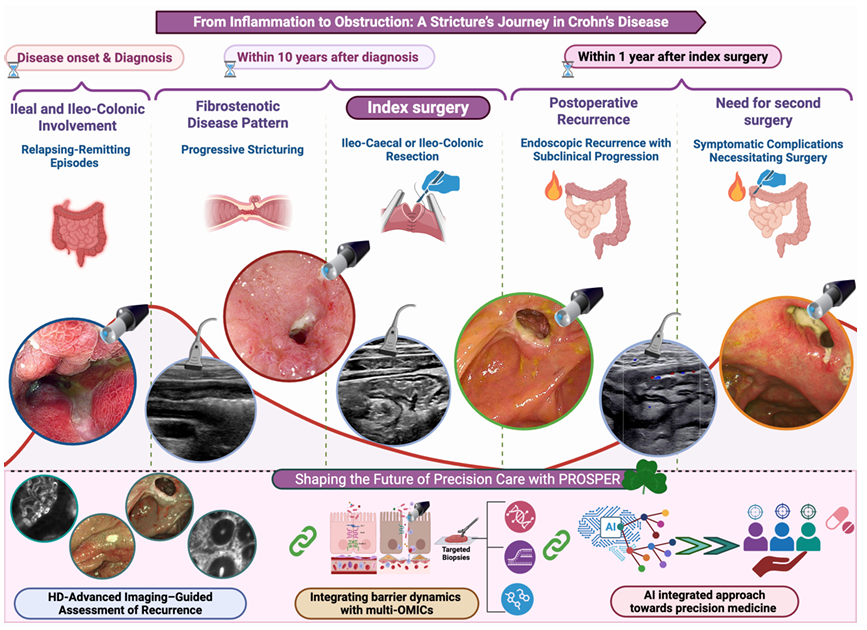

05 (GUT) 塑造克罗恩病术后复发的未来:结合人工智能成像和多组学的个性化方法

5. (Gut,IF:23.0) 塑造克罗恩病术后复发的未来:结合人工智能成像和多组学的个性化方法

5. (Gut,IF:23.0) 塑造克罗恩病术后复发的未来:结合人工智能成像和多组学的个性化方法